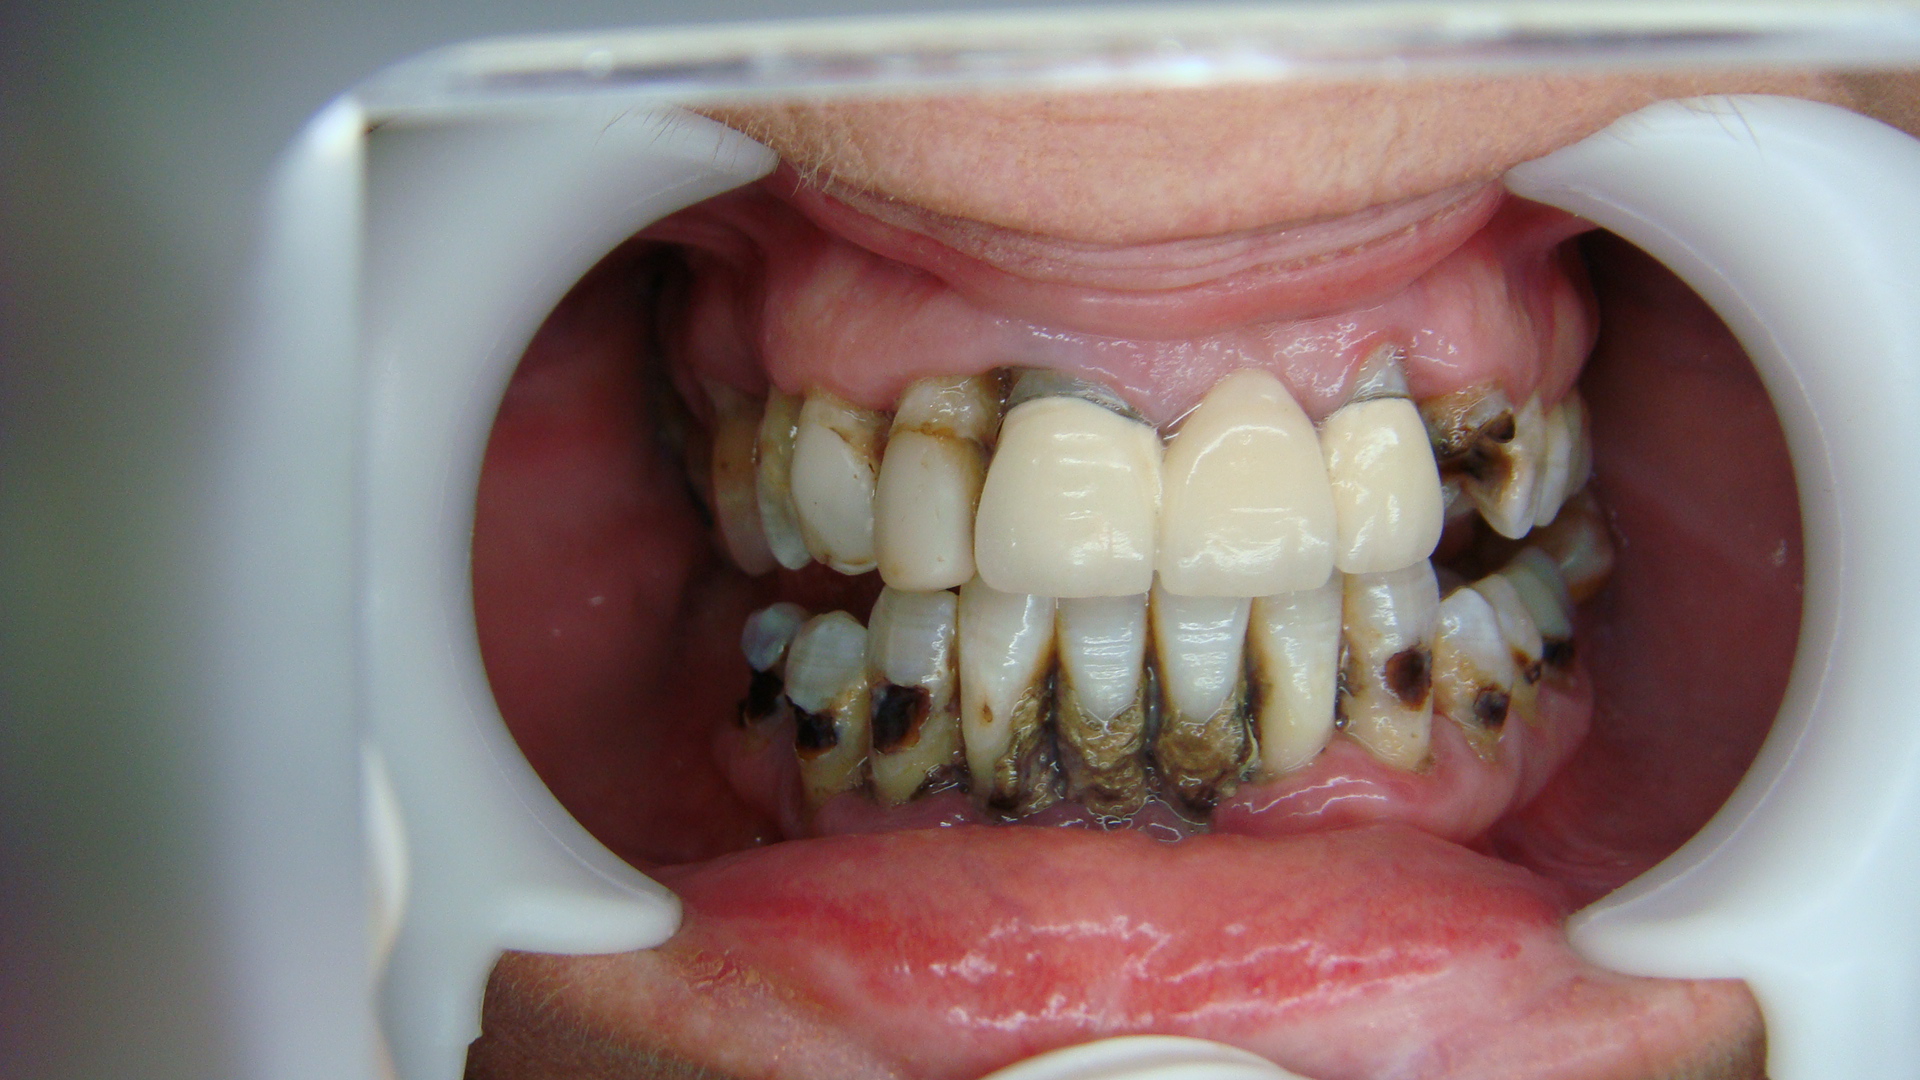

ID Number : 2014-552

Country : Australia

Treatment : Top Teeth : 13 Crowns